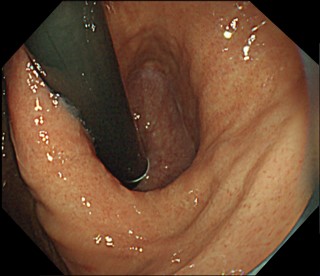

内視鏡で胃と食道のつなぎ目の粘膜を切除して、修復過程で狭くなることを利用して、逆流を防止します。